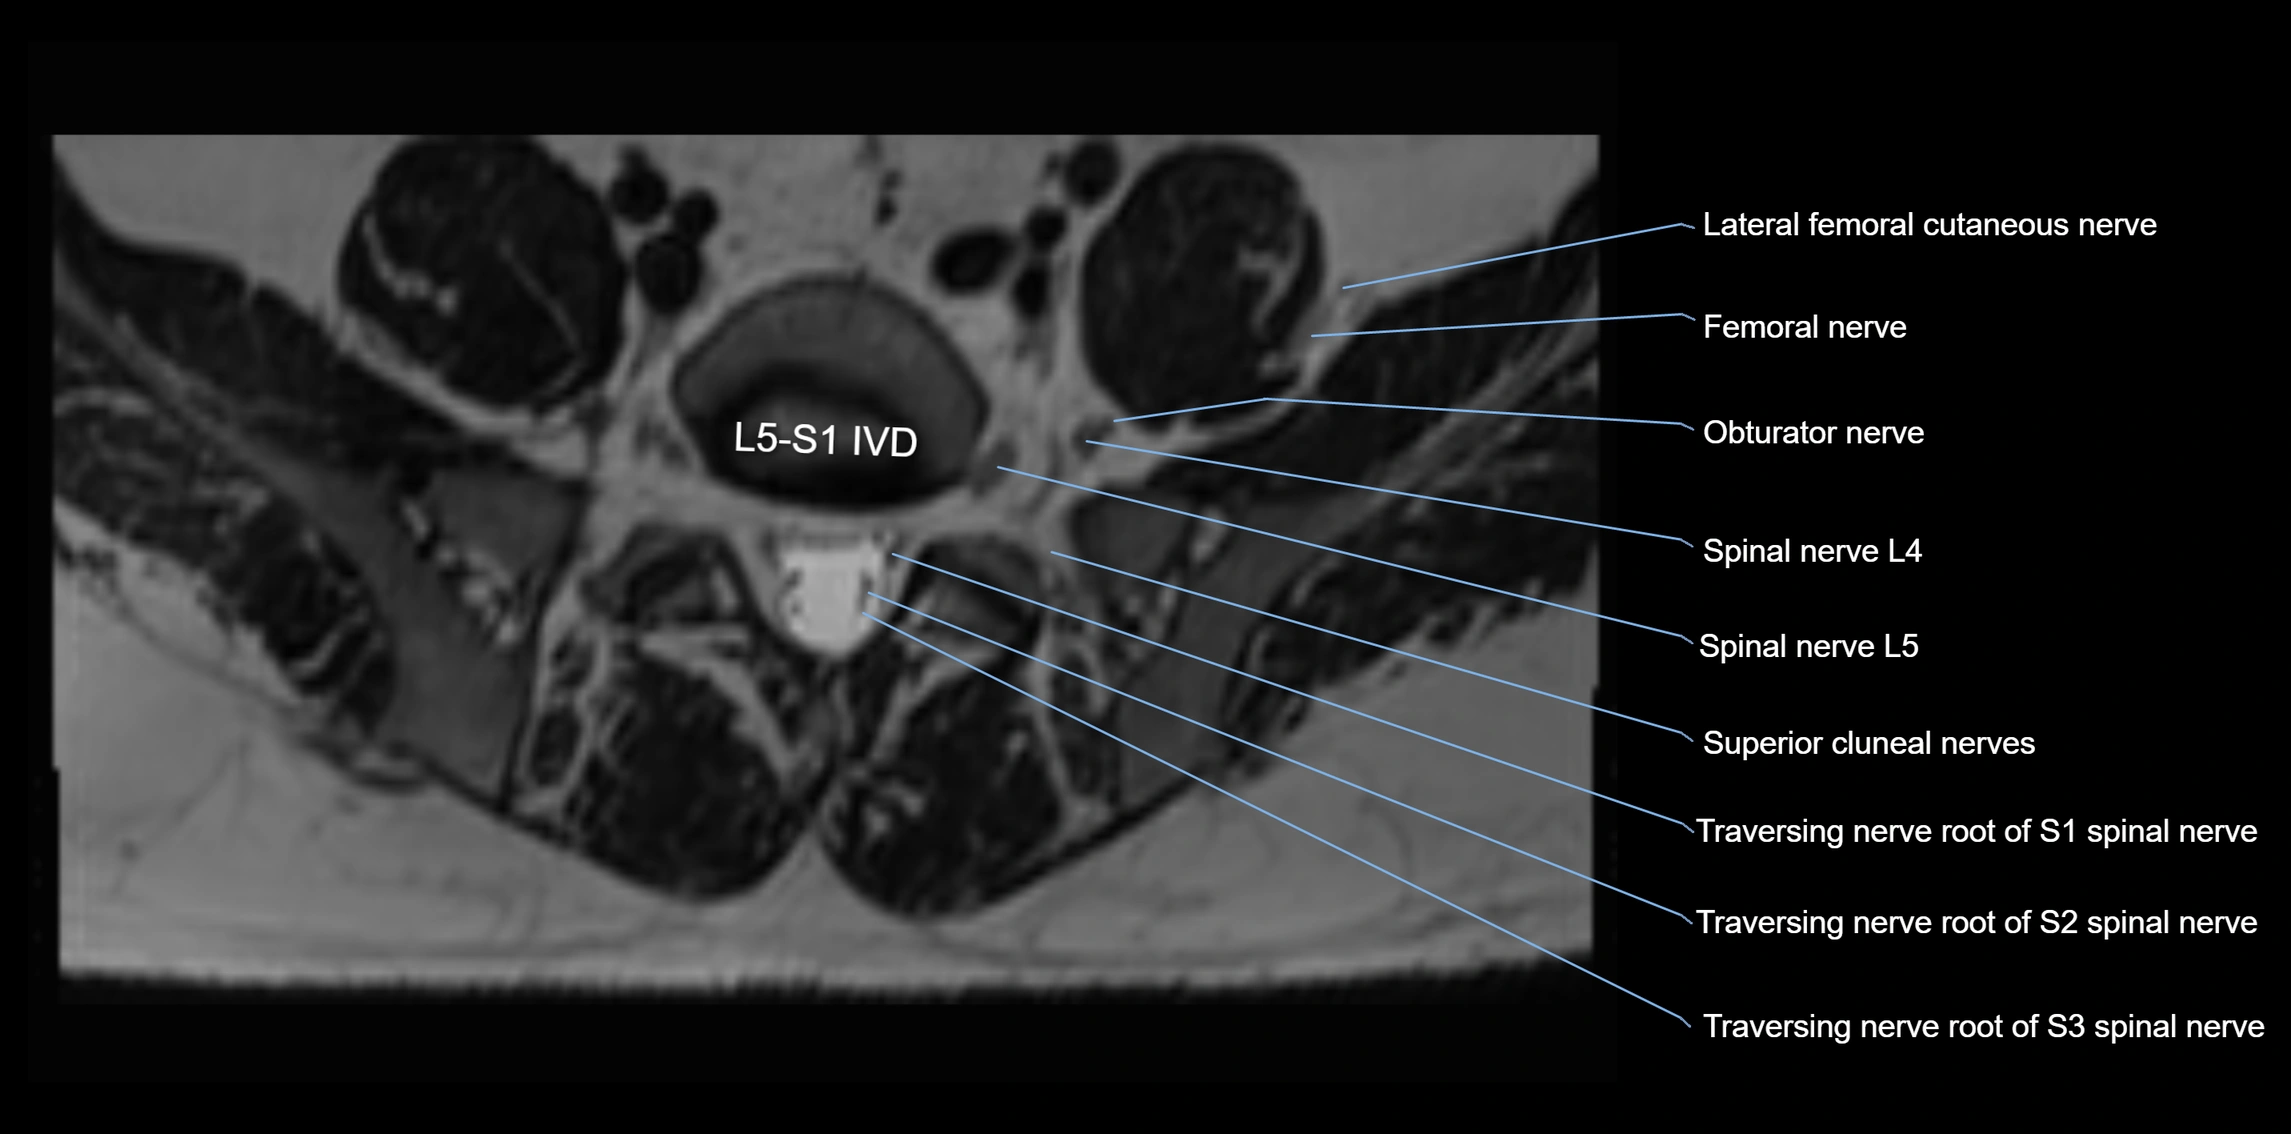

MRI Appearance

T1-weighted images:

• Nerve appears as a very thin low-to-intermediate signal intensity structure

• Surrounded by bright fat, aiding visualization

T2-weighted images:

• Nerve shows intermediate to mildly hyperintense signal compared to muscle

• Pathological involvement appears brighter

STIR (Short Tau Inversion Recovery):

• Normal nerve appears dark

• Inflamed or entrapped nerve appears bright hyperintense

T1 Fat-Sat Post-Contrast:

• Normal nerve enhances minimally

• Pathologic nerve (neuritis, entrapment, tumor infiltration) shows focal or diffuse enhancement

3D T2 SPACE / CISS:

• Nerve appears intermediate to mildly hyperintense compared to muscle

• Surrounded by bright fat or CSF, improving visualization

• Best sequence for mapping small pelvic nerves such as the anococcygeal

MRI image

image